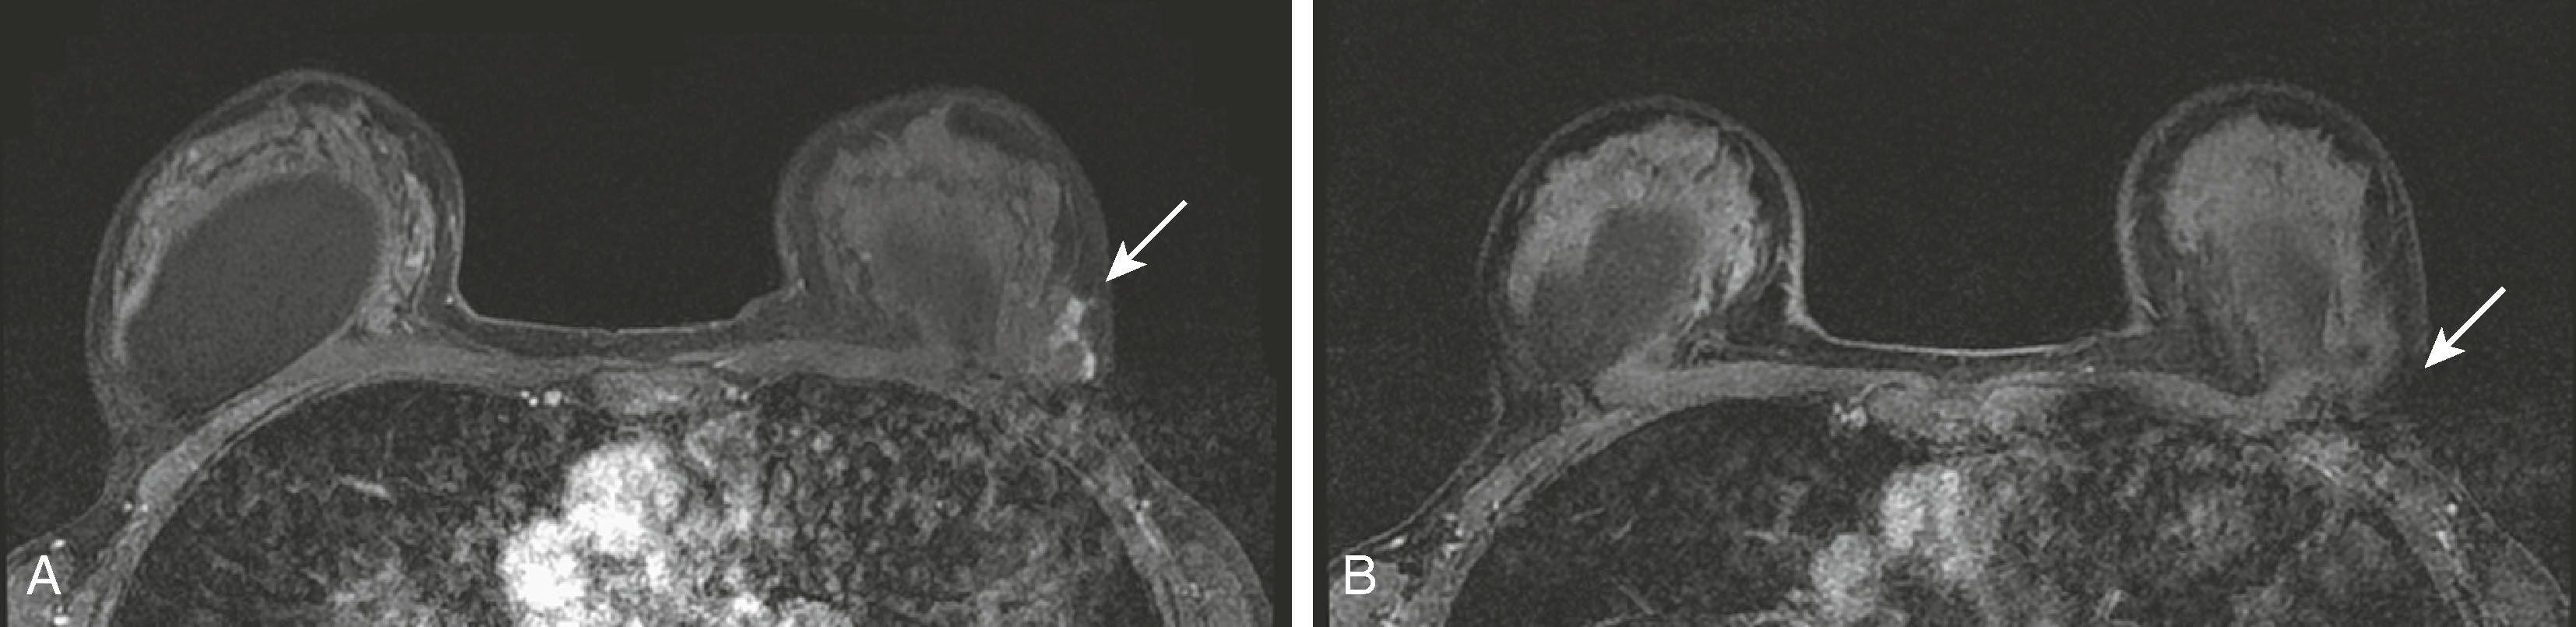

A confounding factor to be considered with MRI is the presence of physiological enhancement, a feature that also affects contrast-enhanced mammography (CEM) and molecular breast imaging (MBI). The enhancement of the breast is subject to physiological changes based on the hormonal status during the menstrual cycle or during pregnancy and lactation. At times, this type of enhancement can mimic cancer. Previously, it has been recommended that when MRI is completely elective, such as when it is performed for high-risk screening, it should be performed during the first week or so of the menstrual cycle. However, this practice is falling out of favor today. When a newly diagnosed breast cancer patient is scanned, it may not be possible to wait for the beginning of the cycle because treatment could be delayed. In addition, women who have had hysterectomy are problematic because the menstrual cycle is not apparent. Figs. 8.24 and 8.25 demonstrate these points in two different clinical scenarios.

Fig. 8.24, ( A ) Breast magnetic resonance imaging (MRI) performed in the latter part of the menstrual cycle demonstrates enhancement in the lateral aspect of the patient’s breast (arrow) . ( B ) The patient had a repeat MRI in the first half of her menstrual cycle, and the physiological enhancement is no longer visible (arrow) .

Fig. 8.25, ( A ) Post-partum patient has a palpable abnormality marked by the triangle (arrow) . ( B ) Magnetic resonance imaging shows physiological enhancement (arrow) related to post-partum state. ( C ) Physiological enhancement partially obscures an enhancing lesion (open arrow) within the medial left breast. ( D ) A second-look ultrasound was performed and demonstrated a hypoechoic lesion with lobulated margins (arrow) .